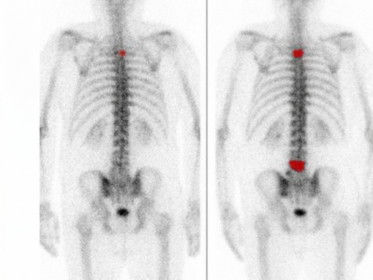

Scintigrafia ossea: evoluzione fisiopatologica, metodologia clinica e analisi avanzata

La scintigrafia ossea rappresenta una delle metodiche più consolidate e versatili nel panorama della medicina nucleare diagnostica. Sin dalla sua introduzione clinica, favorita dalla scoperta del tecnezio-99m metilendifosfonato (99mTc-MDP) da parte di Subramanian e McAfee nel 1971, questa tecnica ha ridefinito la capacità dei clinici di osservare i processi biologici dello scheletro ben prima che…